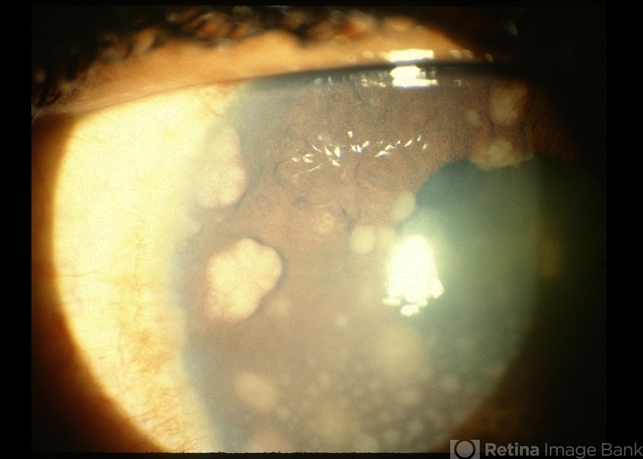

- sarcoid bussaca iris nodules, sarcoidosis, autoimmunity

- Sarcoid bussaca iris nodules.